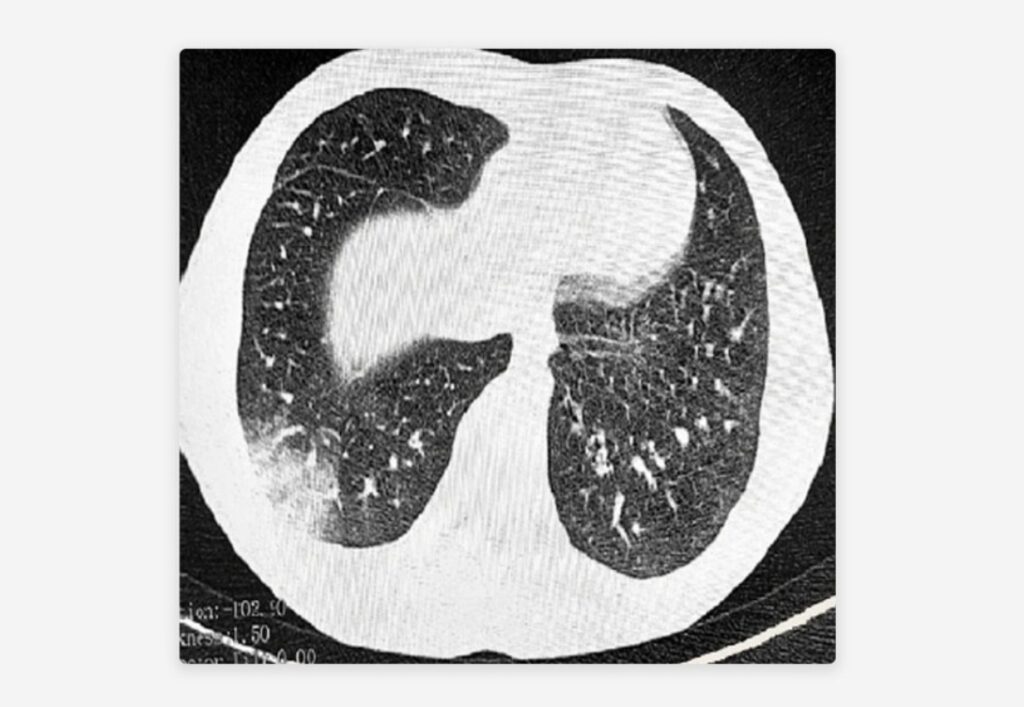

La afección se origina en las vías respiratorias pequeñas, llamadas bronquiolos, y se presenta en forma de inflamación, cicatrización y estrechamiento de estos. Los síntomas incluyen problemas respiratorios como dificultad para respirar, tos y sibilancias.

La enfermedad se revela examinando los pulmones, que emiten un sonido parecido al crujido que hacen las palomitas de maíz cuando estallan. En casos graves, los pacientes son ingresados en unidades de cuidados intensivos y requieren ventilación mecánica.